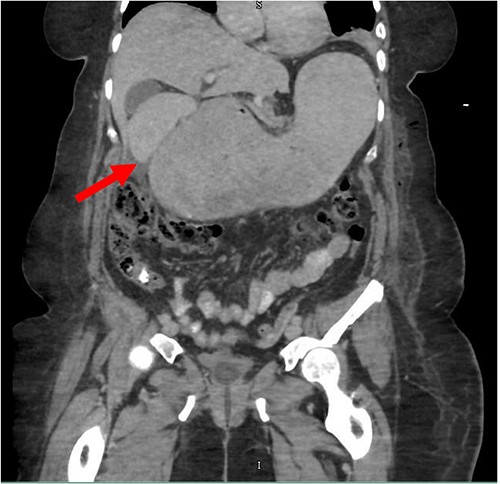

Despite the insertion of the NGT yielding 1500 cc output in 24 hours, the patient continued to experience severe abdominal pain. Urgent abdominal and pelvic computed tomography (CT) scans were taken, as seen in Figs 2–4. The CT scans showed gastric distension and the spleen positioned anteriorly in the right upper quadrant. Consequently, the decision was made to promptly bring the patient to the operating room for a diagnostic laparoscopy with plan to detorse the spleen.

CT of the abdomen and pelvis (sagittal slice) showing gastric distention and the spleen positioned anteriorly.